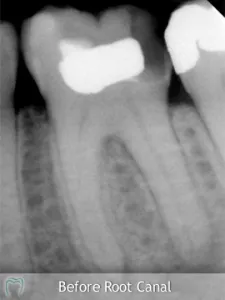

Root Canal Treatment (known as “Endondontic Treatment”) involves the treatment of disease or injury to the dental pulp or ‘nerve in the tooth’. This nerve is located in the very centre of the tooth in a small narrow ‘canal space’ which extends from the crown to the tip of the root – the area inside the centre of each tooth that contains nerves and blood vessels that help nourish the tooth. If the nerve is injured or diseased then it can die and this often leads to sensitivity, toothache or a dental abscess. It can also lead to the tooth actually discolouring.

Root canal treatment saves teeth that would otherwise need to be extracted. It involves removing the damaged or dead nerve tissues and pus in the root canals of teeth that have become infected. The infected or dead tissue is cleaned away and the residual canal space is also cleaned and disinfected, and the root canal is prepared so that it can be sealed with a filling. The tooth can then be restored and can remain in function for many years provided there is sufficient sound tooth structure to support a new filling or crown.